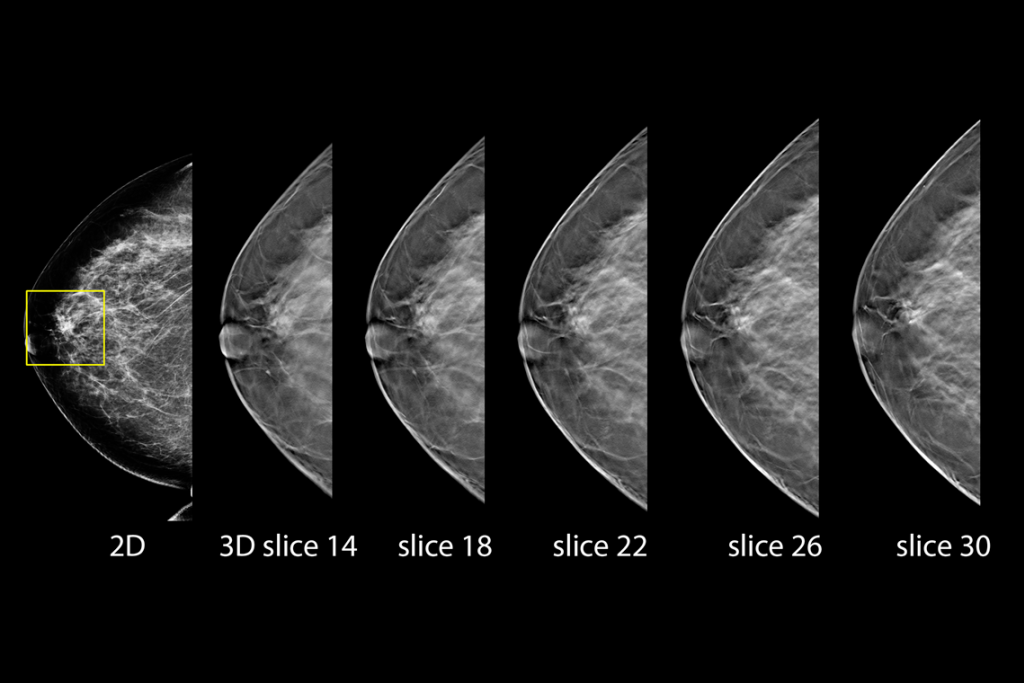

Imágenes clínicas de una mamografía

Imágenes clínicas de una mamografía con una lesión sospechosa